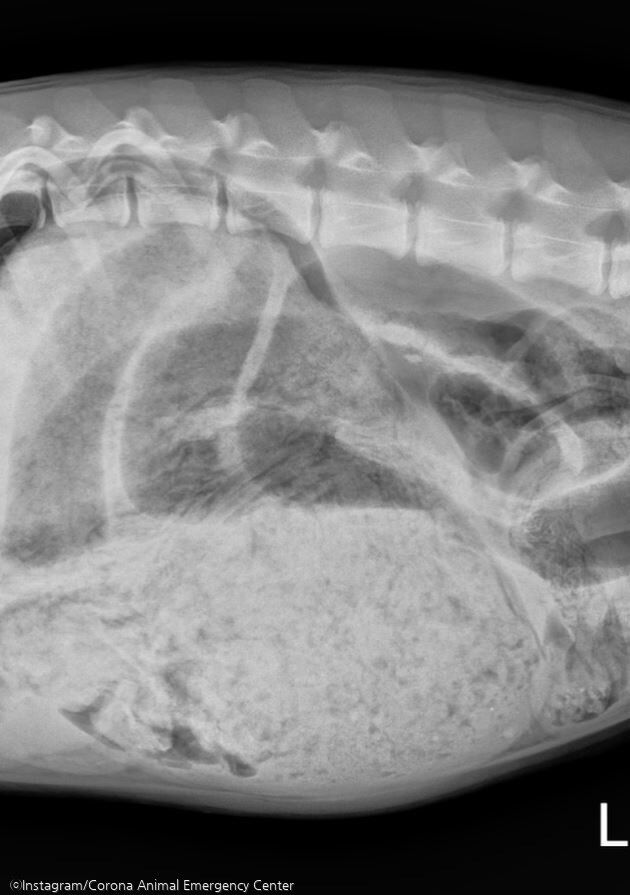

매체에 따르면, 미국 캘리포니아주 코로나에 위치한 동물병원 'Corona Animal Emergency Center'는 최근 7개월 생 암컷 버니즈 마운틴독 '루나(Luna)'를 진찰했다.

앞서 루나의 가족은 녀석이 구토를 하자 병원으로 데려갔다. 당시 루나의 복부는 딱딱했으며 팽창된 상태였다는데.

의료진은 루나를 검사하다가 배 속에 있어선 안 될 물건들을 발견했다. 믿을 수 없게도, 루나의 위는 녀석이 삼킨 양말 24켤레와 머리끈, 천 조각들로 채워져 있었다.

심지어 루나는 신발 깔창과 옷까지 먹은 상태였다. 먹어선 안 될 이물질을 많이 먹은 대가로 루나는 수술을 받아야 했다.

의료진은 위를 절개해서 이물질을 제거하는 등 대대적인 수술을 진행했다. 병원 측이 지난 25일 공식 인스타그램에 공개한 사진은 루나의 배에서 나온 이물질을 보여준다.